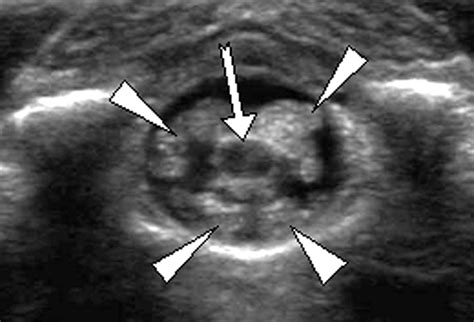

• Imaging Studies: X-rays, MRI, or CT scans to visualize the spinal cord and surrounding structures.

• Ultrasound: To assess for the presence of cysts or other abnormalities.